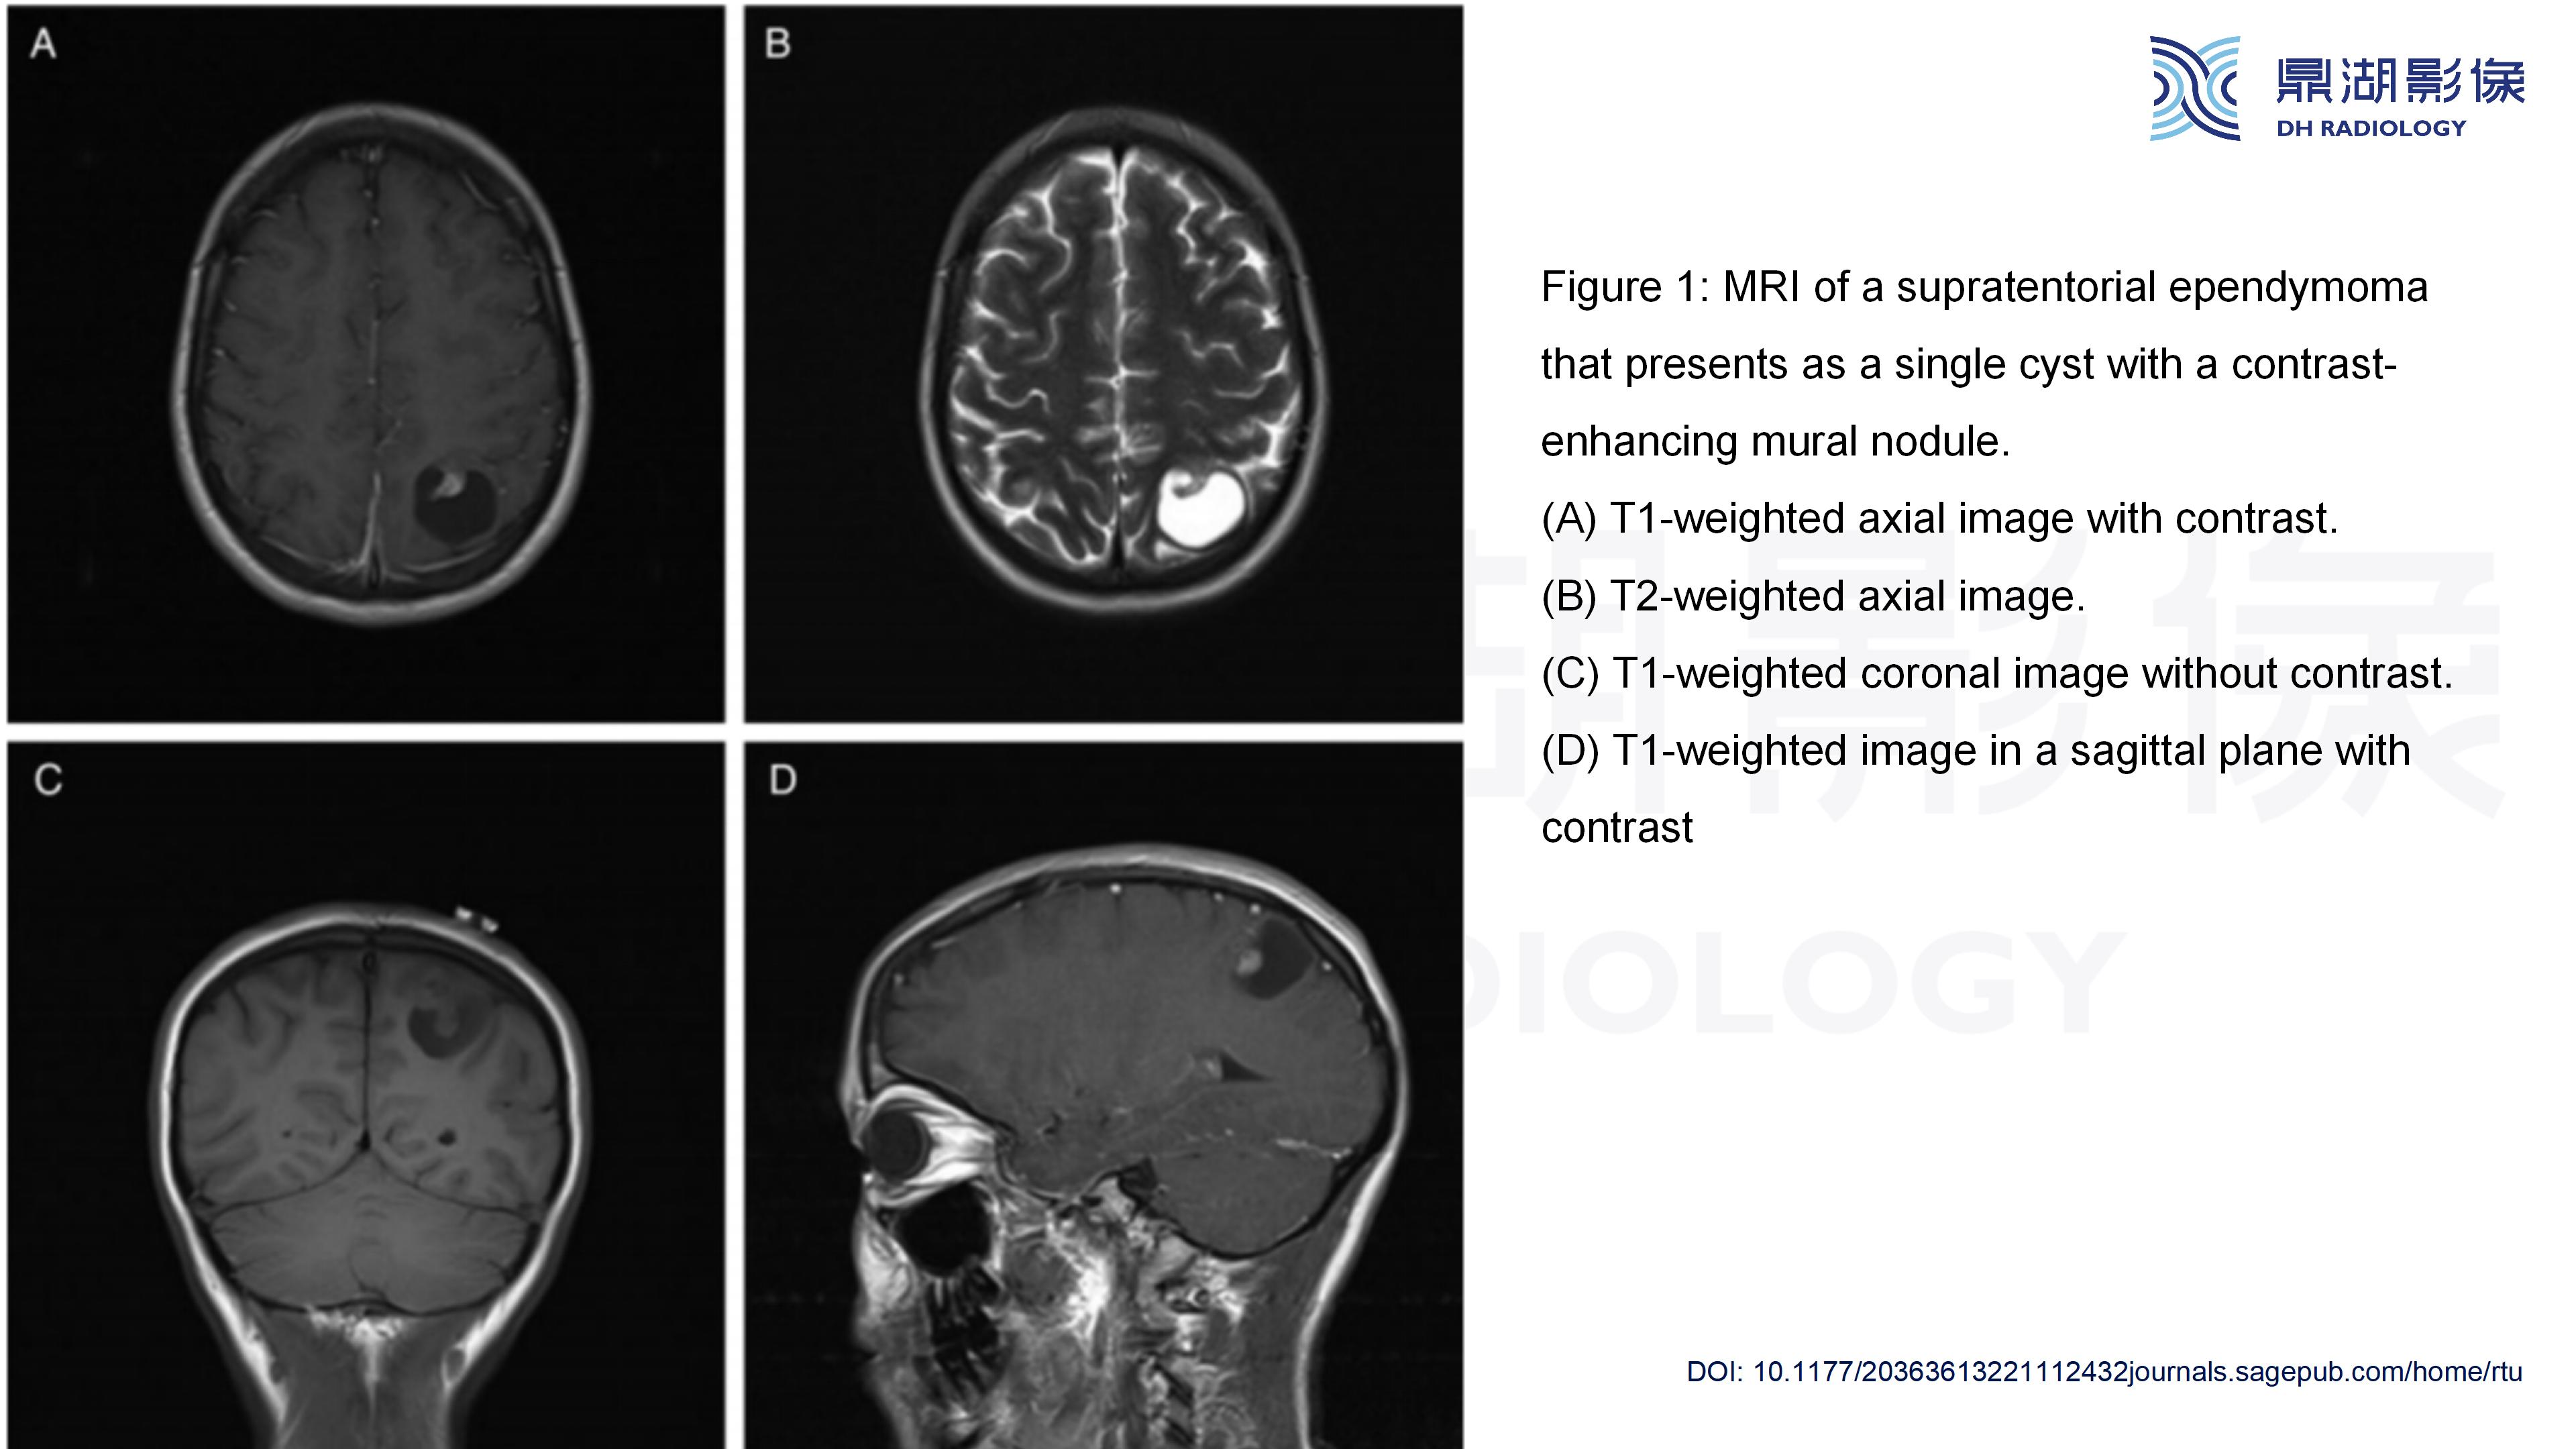

幕上毛细胞型星形细胞瘤(WHO Ⅰ级)